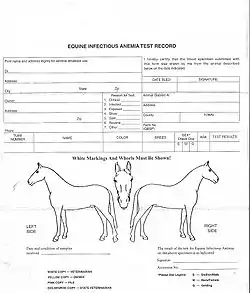

The Coggins test (agar immunodiffusion) is a sensitive diagnostic test for equine infectious anemia developed by Dr. Leroy Coggins in the 1970s.

Currently, the US does not have an eradication program due to the low rate of incidence. However, many states require a negative Coggins test for interstate travel. In addition, most horse shows and events require a negative Coggins test. Most countries require a negative test result before allowing an imported horse into the country.

Horse owners should verify that all the horses at a breeding farm and or boarding facility have a negative Coggins test before using the services of the facility. A Coggins test should be done on an annual basis. Tests every 6 months are recommended if there is increased traveling.